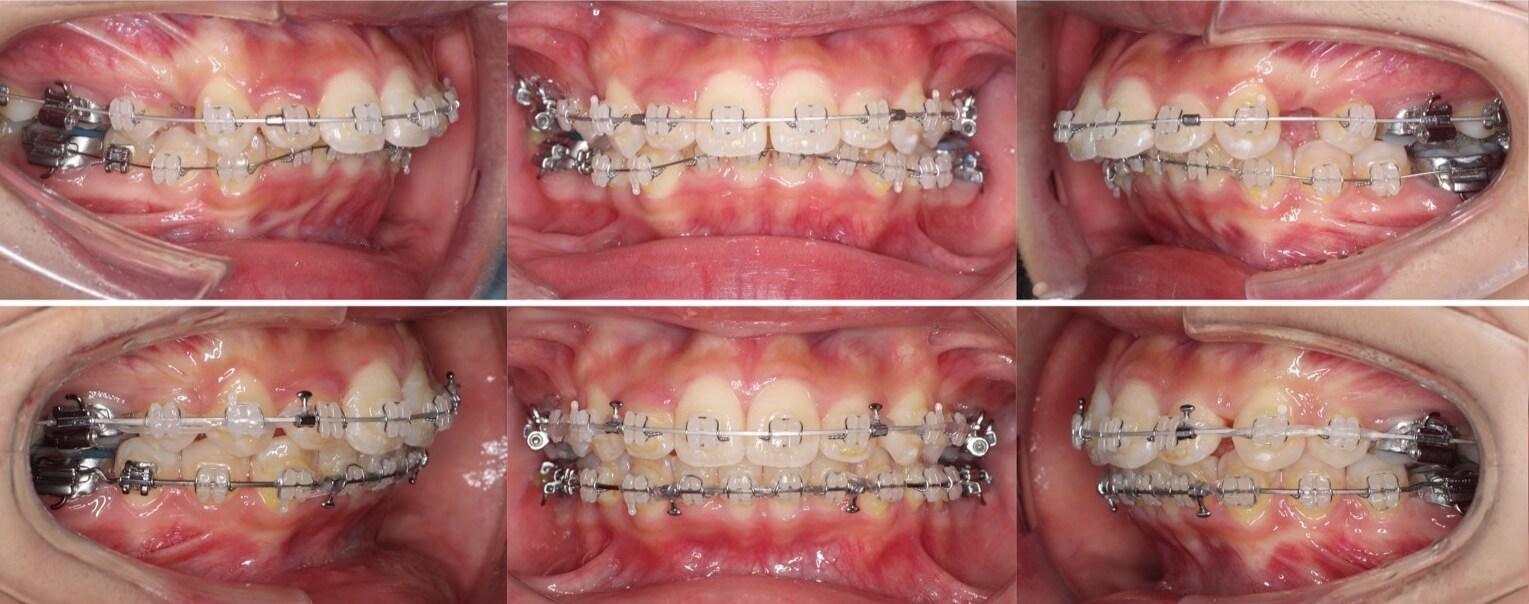

高校生女性・マウスピース型装置・遠心移動

途中で、右下前歯がアンフィットしてしまったため、フックを設置しマウスピースを覆うようにゴムをかけてリカバリーを行いました。お住まいが遠方になってしまい、中々通院回数を確保する事ができなかったのですが、何とか治療を終了する事ができました。

<症例概要> 難易度★★☆☆☆

主訴:出っ歯

年齢・性別:高校生女子

住まい:千葉県八千代市

症状:上顎前突・叢生

治療方針:上顎後方移動・ストリッピング

治療装置:マウスピース型矯正装置(アライナー装置)

治療期間:1年10か月(1週間交換)

アライナー枚数:60+29ステージ

リテーナー:上下クリアタイプ+上フィックスタイプ

治療費用:990,000(税込)

代表的副作用:痛み・治療後の後戻り・歯根吸収・歯髄壊死・歯肉退縮

II級ゴムを使用して、上顎を順々に遠心移動していく方針です。